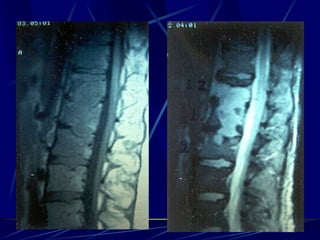

T.B.C.

Φυματίωση της σπονδυλικής στήλης